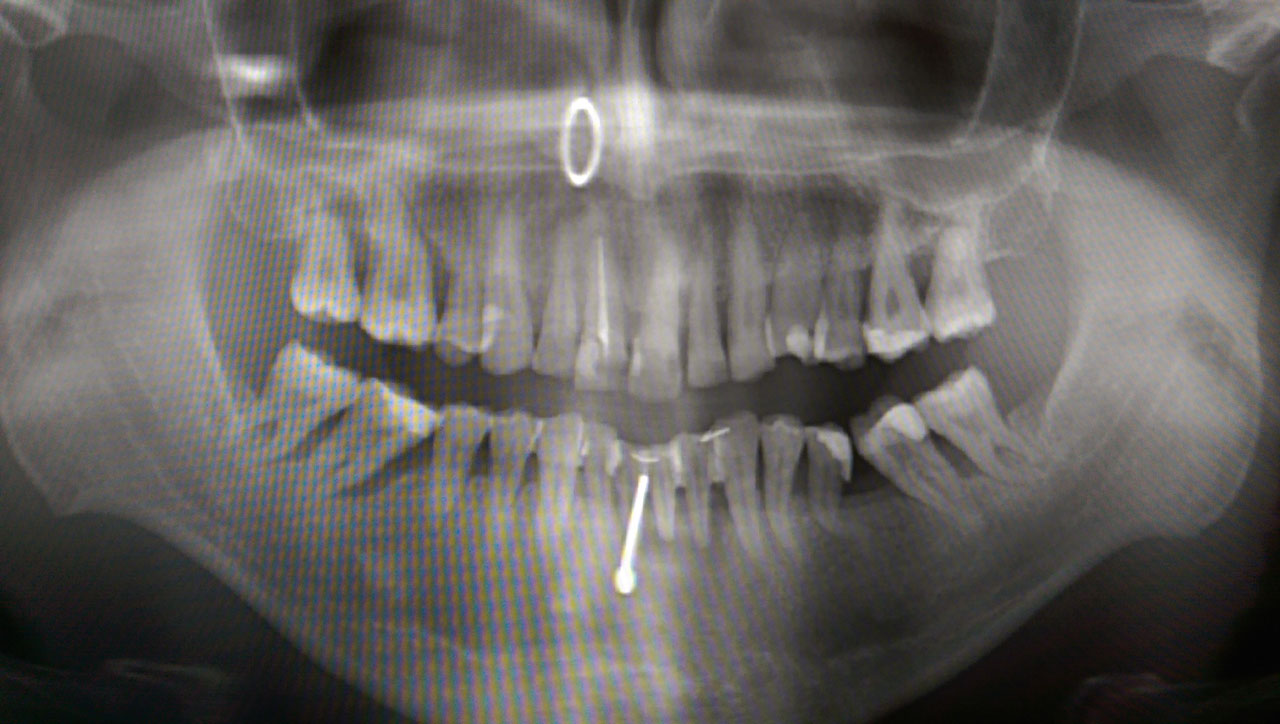

Elhanyagolt fogsor cseréje 2 nap alatt

2 nap alatt varázsoltuk ezt a szép esztétikus alsó, felső körhídat implantátumokkal megtámasztva a korábban elhanyagolt szájba. Az 1. nap 26 fogat távolítottunk el, mert annyira rossz állapotban voltak, és rögtön azonnal terhelhető IHDE svájci implantátumokat raktunk be, fentre 8, lentre 6 darabot. A sebeket összevarrtuk és intraorális szkennerrel digitális lenyomatot vettünk. 2 nap múlva pedig beragasztottuk a kész PMMA műanyag körhidakat. Dr. Kelemen Péter és a Symbion Fogtechnika munkája.